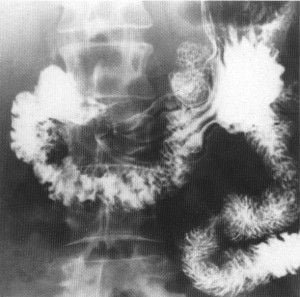

Noticias y Articulos Tránsito esofagogastroduodenal (E.G.D.) – Parte II 21 junio, 2012 Tidito Imágenes Transito Esofagogastroduodenal (E.G.D.) Seriadas Bulbares Duodeno en Anteroposterior